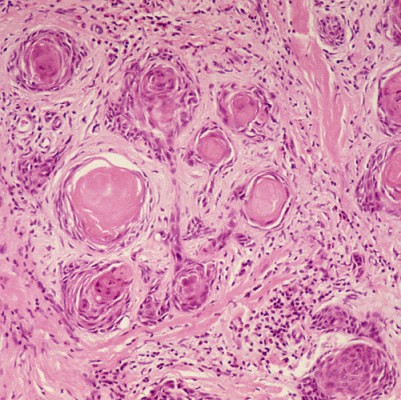

Squamous Cell Carcinoma

General

Primary cause of all skin cancers: Over 90% of skin cancers occur on areas of the skin that are regularly exposed to sunlight or other ultraviolet radiation.

4. Squamous cell carcinoma occurs in the elderly, especially fair-skinned individuals.

5. It has the potential form distant or regional metastasis.

Location and Symptoms

It is most common along the lower eyelid margin. It occurs more often than basal cell in the upper lid and outer canthus. It represents only 5% of lid epithelial tumors.

Growth or Bump

1. Size: small​

2. Texture: firm, surface scaly or crusted

3. Color: reddened

4. Shape: flat or nodu

Treatment

1. Treatment consists of wide local excision.

2. Microscopic shaving (Mohs’ surgery) could remove small tumors.

3. Skin grafts could be needed if wide areas of skin are removed